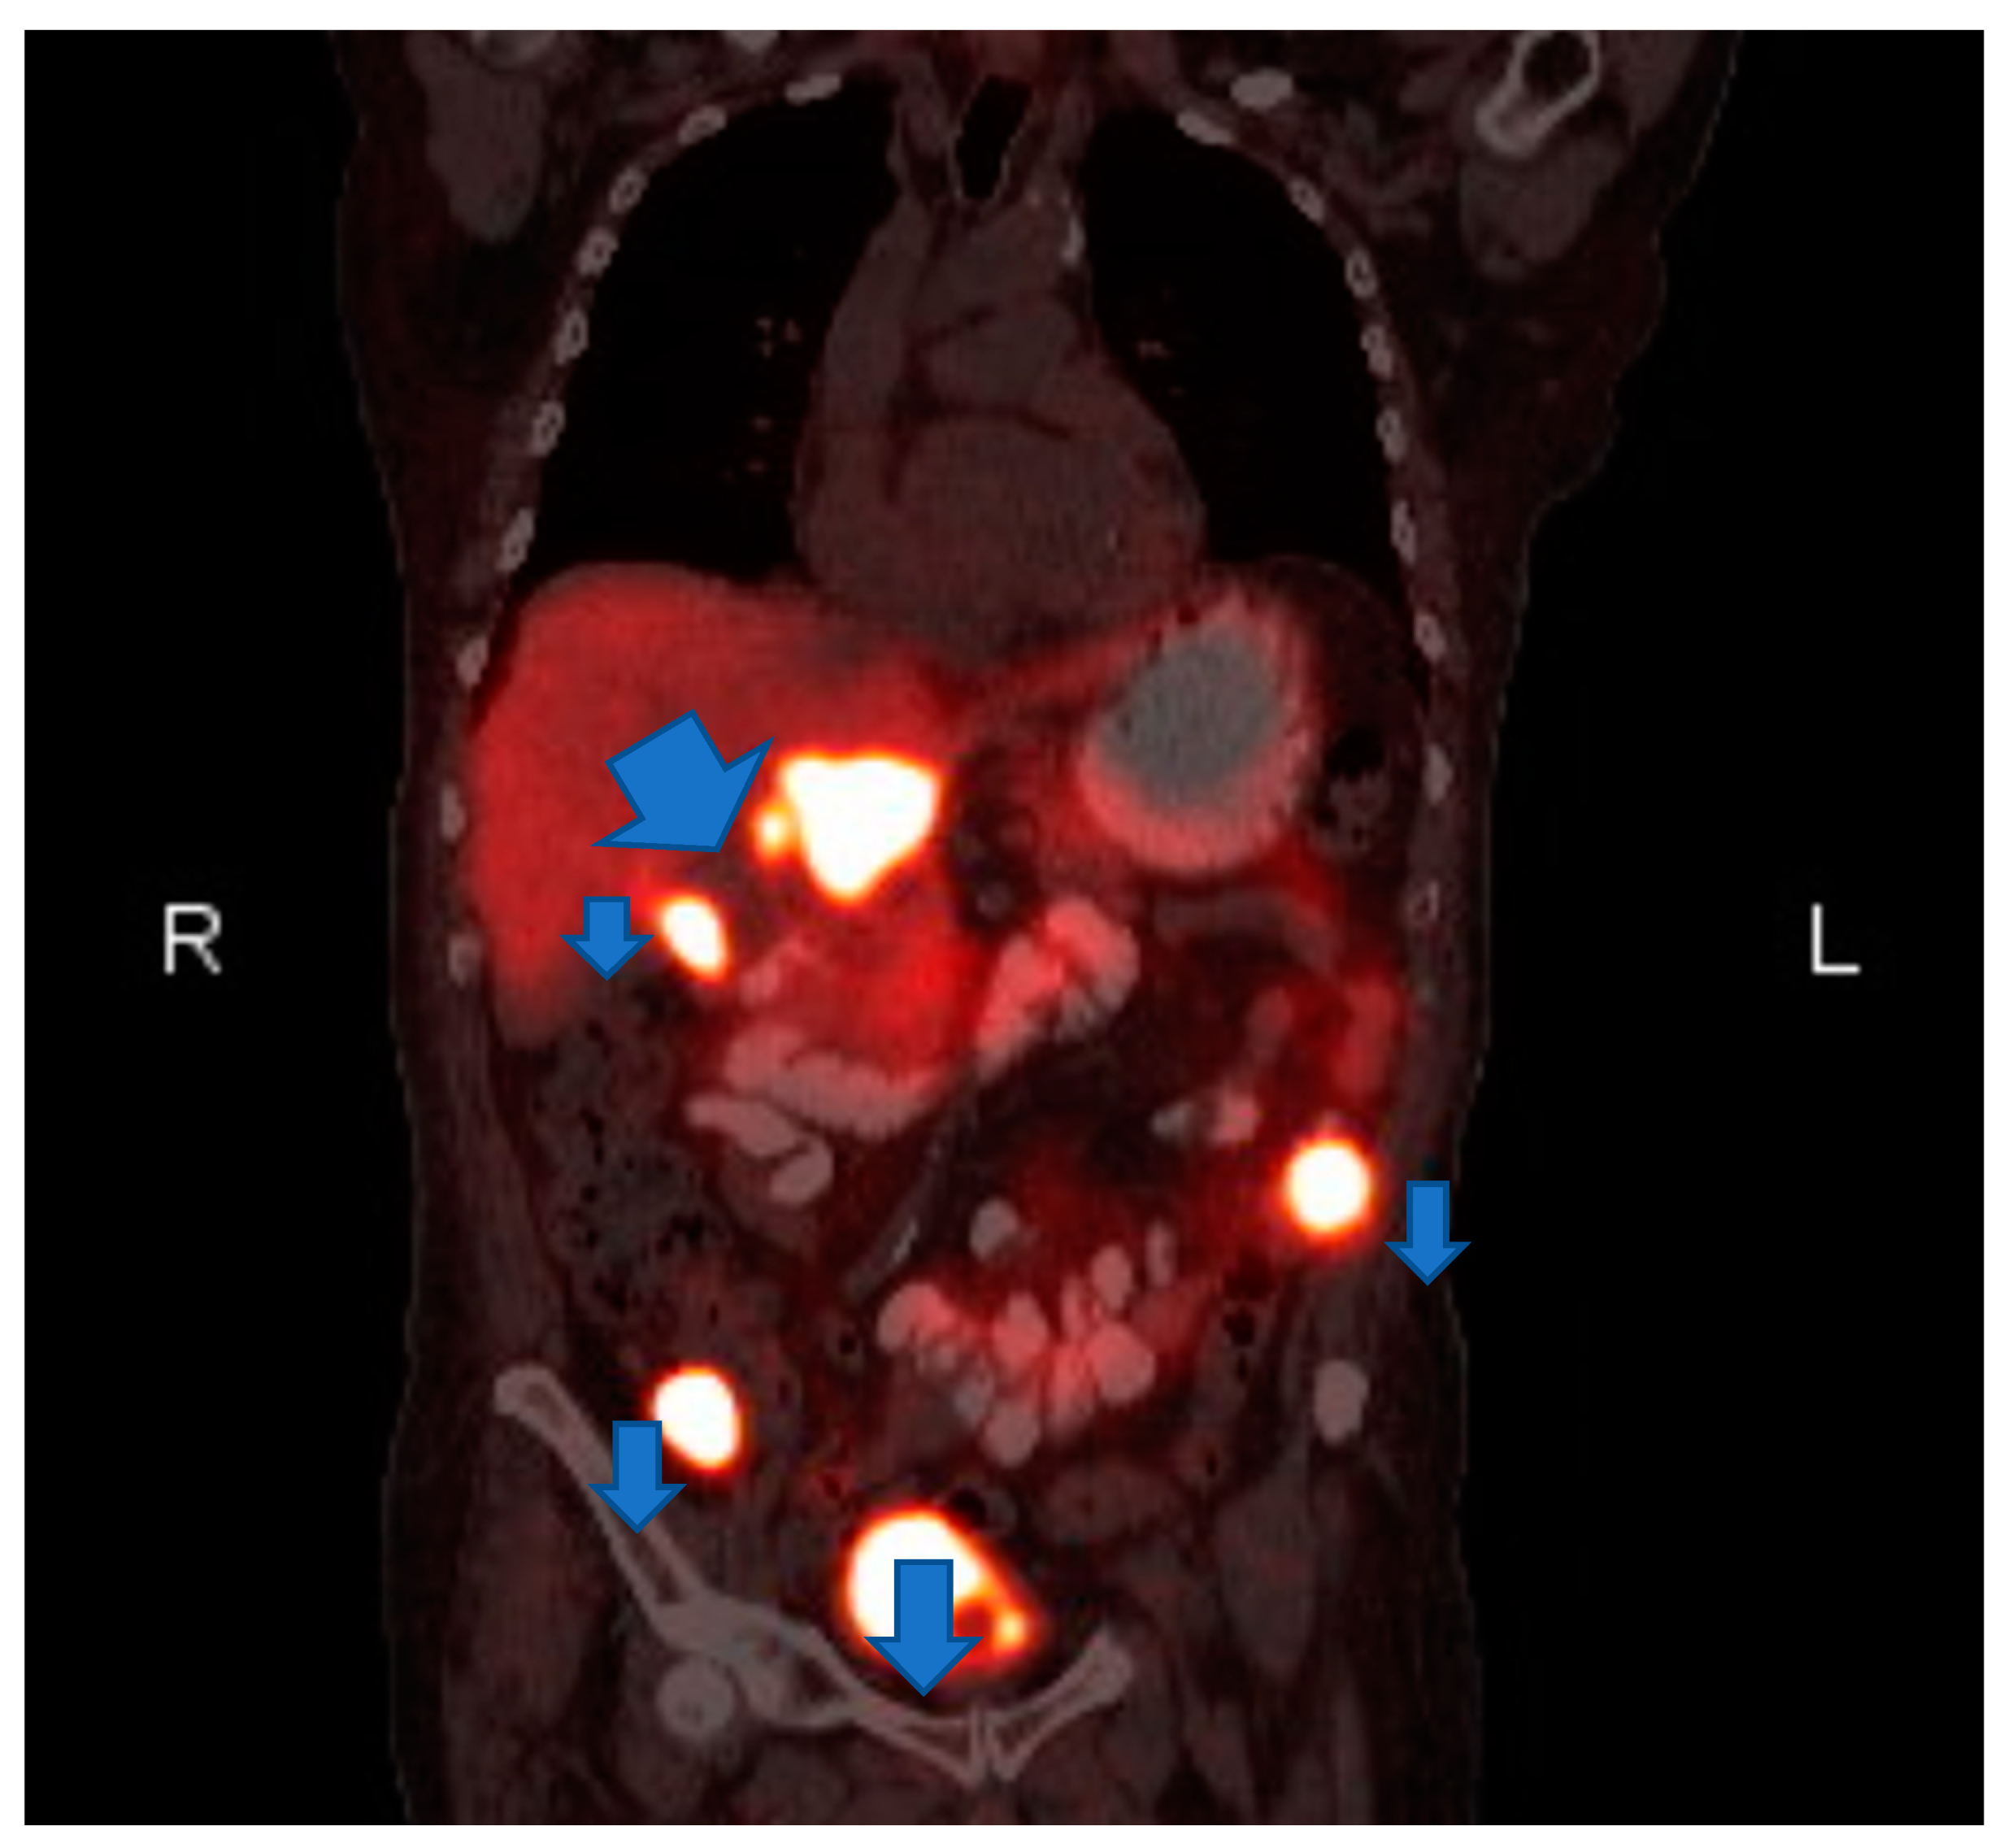

Laboratory testing revealed anemia (hemoglobin 9.2 g/dl) and hyponatremia (sodium 131). His urine metanephrine was 556 mcg/24 h, normetanephrine was 22,624 mcg/24 h and creatinine was 2.56 mg/dl. His INR was 4.26 which was high. On imaging, there was an abdominal mass on the right upper kidney as well as an abdominal hematoma. Computer tomography (CT) of abdomen showed left lower abdominal wall hematoma and prominent multilobulated soft tissue mass within the right retroperitoneum superior to the right kidney in the region of right adrenal gland involving the liver, vena cava and kidney. Magnetic resonance imaging (MRI) of abdomen and pelvis showed postoperative changes after right adrenalectomy with 7.8 cm heterogenous multilocular enhancing mass in the surgical bed abutting the right posterior wall and close to the right kidney and Inferior vena cava (IVC). The mass and the enlarged regional lymph nodes together caused marked compression of the IVC. Heterogeneity and enhancing focus in the posterior right hepatic lobe indicated the invasion of the right adrenal gland. (Figure 1) Positron emission tomography (PET) gallium-68 DOTA-DPhe1, Tyr3-octreotate ((68Ga)Ga-DOTA-TATE) imaging showed liver and mesentery metastases. (Figure 2) He was diagnosed with right metastatic malignant adrenal lesion surrounding IVC along with the syndrome of inappropriate antidiuretic hormone (SIADH).

Figure 2.

Coronal Postitron Emission Tomography/Computed Tomography (PET/CT). gallium-68 DOTA-DPhe1, Tyr3-octreotate (68Ga)Ga-DOTA-TATE Abnormal gallium dotatate accumulation in the right adrenalectomy bed, upper abdominal lymph nodes and two mesenteric nodules.